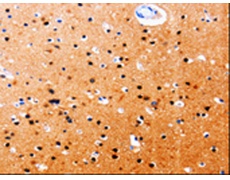

IHC positive control: |

Human brain and Human tonsil |

IHC Recommend dilution: |

25-50 |